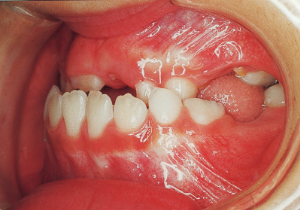

2 After Phase 2 Treatment 5-9-’92

This case presented with Class III malocclusion and significant negative overjet from the early mixed dentition. Regular observation was conducted, and Phase I treatment was initiated after the eruption of the anterior teeth, improving the anterior occlusal relationship and molar relationship. Subsequently, regular observation continued toward the completion of the permanent dentition. However, due to vigorous mandibular growth, orthodontic treatment including surgery became necessary.

Aware that treatment would be challenging, we proceeded with the first phase of treatment based on the current functional status and anticipated developmental implications (7). During the mixed dentition phase, the body responds readily to treatment, allowing for relatively rapid tooth movement and changes in jaw position (8,9). Subsequently, once freed from mechanical stimulation, growth continues according to inherent predispositions, often appearing to disregard occlusal functional efficiency (10,11). These changes are clearly observable on cephalometric radiographs (12). After confirming the extent and direction of growth, we decided to incorporate surgical intervention into the treatment plan and wait until the age when growth begin to decline.